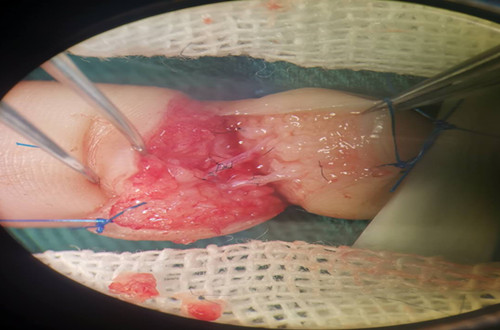

手術(shù)資料如圖示:

侯曉進(jìn)主任帶領(lǐng)醫(yī)師岳賢峰、魏石磊歷時(shí)2小時(shí),成功再植離斷指體。觀察指體張力適中,皮溫、皮色正常,毛細(xì)血管充盈實(shí)驗(yàn)正常。術(shù)后予以對(duì)癥治療,按時(shí)傷口換藥,保持清潔。再植指體存活良好。于2019年1月22日間斷拆除傷口縫線后,患兒治愈出院。